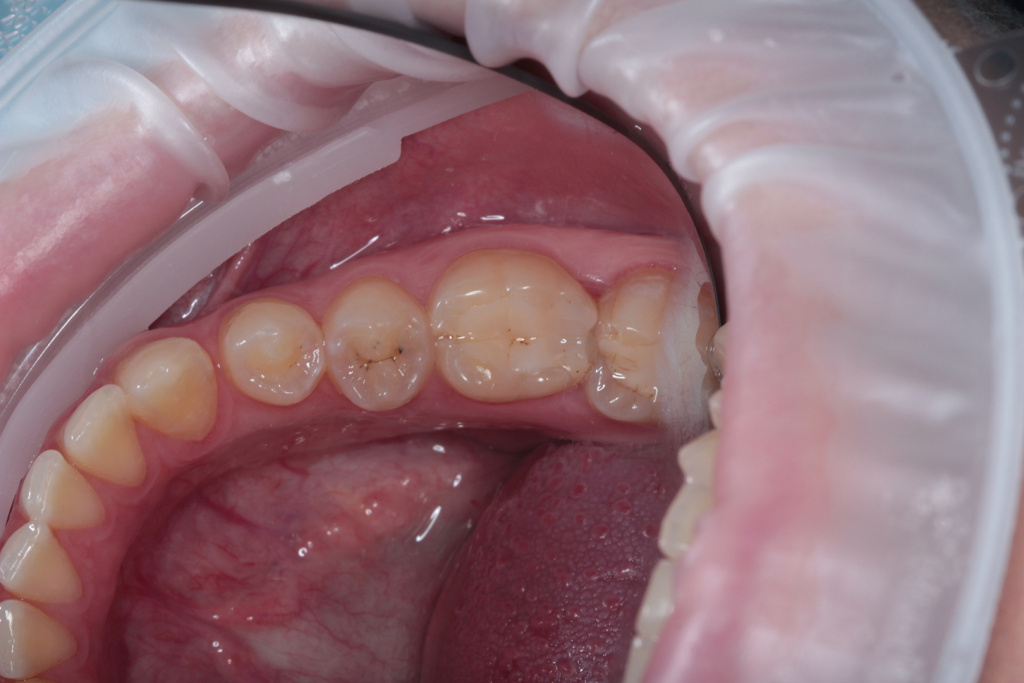

Одноэтапная установка формирователя десны